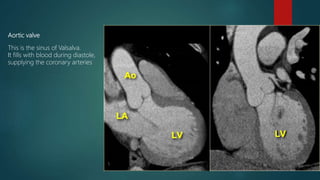

Aortic valve

This is the sinus of Valsalva.

It fills with blood during diastole,

supplying the coronary arteries

Normal Anatomy of the

 Valve consists of three semilunar

cusps

 Between the cusps and wall there

are pocket like sinuses